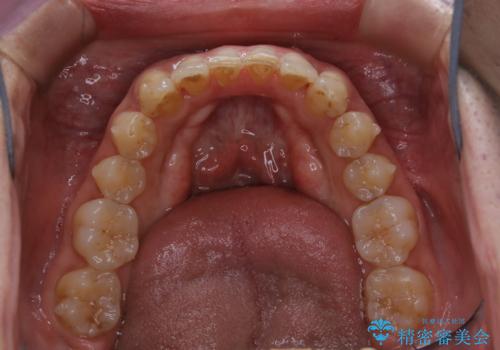

- インビザラインによるマウスピース矯正中に歯の黄ばみ・ステインが気になるとのことでした。PMTC60分コースを行いました。

矯正治療中もPMTCを定期的に行い、専門的な機械でしっかりと汚れを除去することがおススメです。

PMTCは30分コース・60分コースがあります。

60分コースでは全体的に行います。